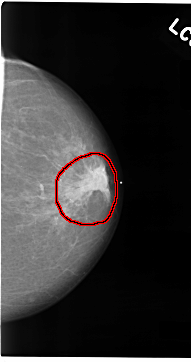

C_0074_1.LEFT_CC

FILE: C_0074_1.LEFT_CC.OVERLAY

TOTAL_ABNORMALITIES 1

ABNORMALITY 1

LESION_TYPE MASS SHAPE IRREGULAR MARGINS SPICULATED

ASSESSMENT 5

SUBTLETY 5

PATHOLOGY MALIGNANT

TOTAL_OUTLINES 1

BOUNDARY